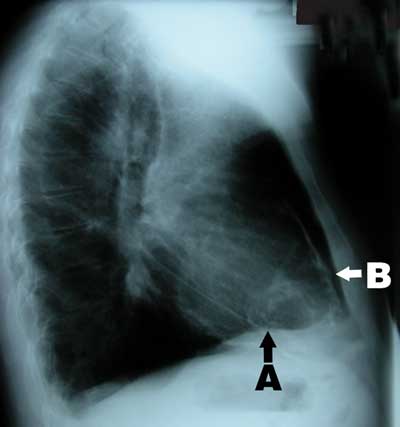

A 58-year-old man of British descent presented in 2003 with chest pain, facial flushing and elevated jugular venous pressure but no leg oedema. He had been exposed to tuberculosis in childhood, had a strongly positive tuberculin test and had been followed up in the tuberculosis surveillance program with regular chest x-rays, but had never been diagnosed with tuberculosis. Chest x-ray on presentation showed calcified plaques and masses in the pericardium and mediastinum (Box 1). Computed tomography revealed extensive calcification of the pericardium (Box 2). Coronary angiography showed 70% stenosis in the left anterior descending artery. Cardiac catheterisation showed equalisation of diastolic pressures in all four chambers, with a positive square root sign (pattern of ventricular diastolic pressure characteristic of constrictive pericarditis).